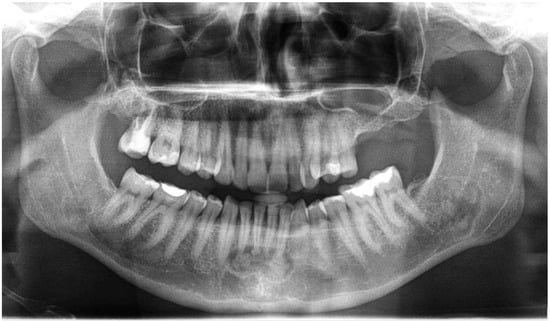

- mixed radiolucent/radiopaque lesion (depending on the stage of COD maturation), Figure 1.

- present in the jaw/maxilla in tooth-bearing areas, Figure 3

- radiolucent with/without radio-opacities with thin radiolucent rim, Figure 2

- self-limiting radiolucency, Figure 4

- associated with anterior/posterior teeth (Figure 2)

- various stages of calcifying masses inside of the lesion, Figure 5

- may cause cortical expansion or teeth displacement, Figure 5.

- no changes within the teeth root apex, Figure 3